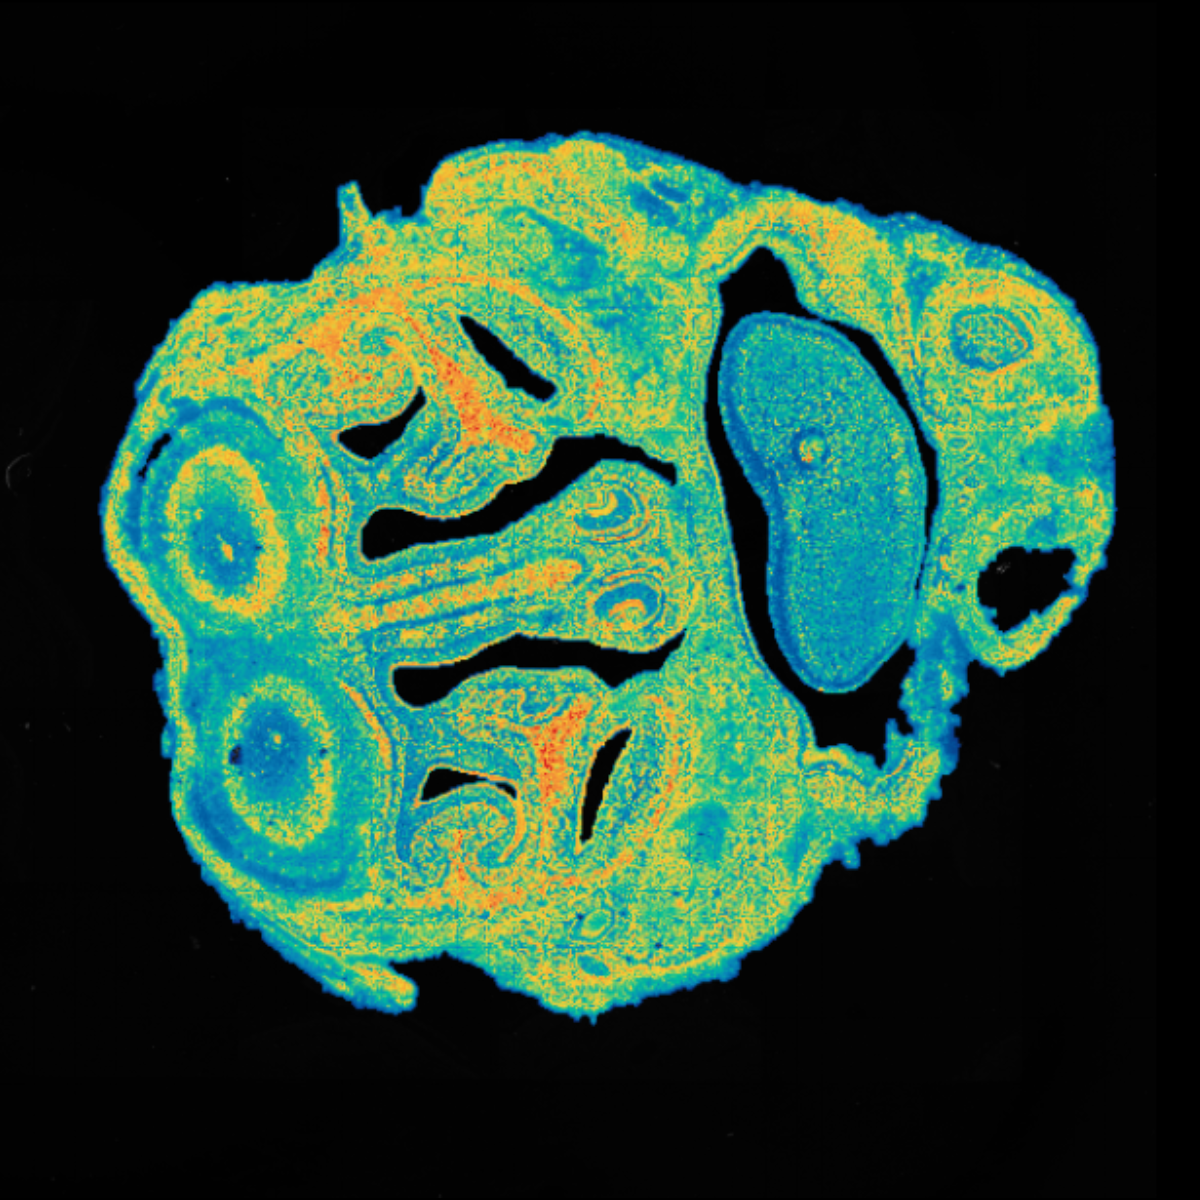

Sample Type: FFPE

Sample Origin: monkey brain

Platform: Stereo-seq OMNI